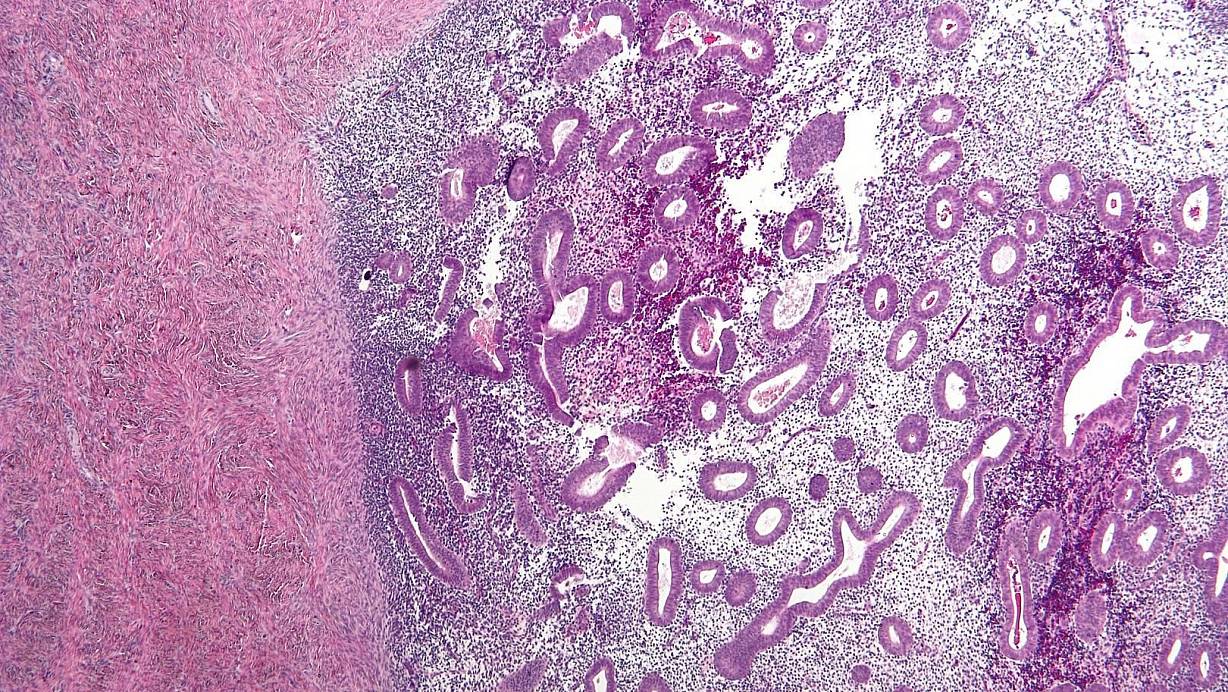

So sieht eine Endometriose unter dem Mikroskop aus. | © Wikipedia

Das Klinikforum im Livestream startet um 19 Uhr auf Facebook, Instagram und YouTube (Links im Infokasten). Das Thema lautet: „Endometriose: Schmerzen müssen nicht zum Leben gehören ". Es geht um eine noch immer vielen unbekannte aber durchaus gefährliche Frauenkrankheit. Bei der Endometriose treten Zysten und Entzündungen auf. Diese können unter anderem Eierstöcke, Darm oder Bauchfell betreffen und zudem große Schmerzen verursachen. Endometrioseherde können im schlimmsten Fall sogar metastasieren und bleibende Schäden an Organen verursachen.